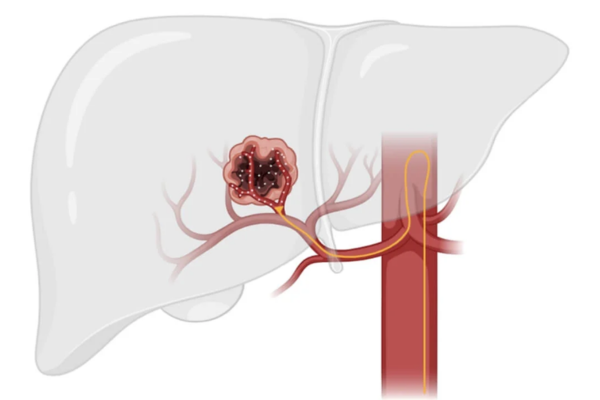

Hepatocellular carcinoma is a primary liver cancer often associated with cirrhosis or chronic liver disease. Surgery may not be possible in many patients.

TACE delivers chemotherapy directly to the tumor and blocks its blood supply, slowing growth while preserving healthy liver tissue.